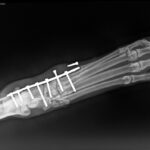

darf ich Euch unseren tapferen Kater Filou vorstellen? Der charmante, weiß-getigerte Kater hatte vor zwei Jahren einen schlimmen Unfall, bei dem sein Mittelfußgelenk schwer verletzt wurde. Dank einer Operation, bei der das Gelenk versteift und eine Metallplatte eingesetzt wurde, konnte Filou damals gerettet werden.

Doch jetzt braucht er erneut Eure Hilfe: Die Schrauben in seinem Bein haben sich gelockert und Filou hat große Schmerzen.

Die Platte muss dringend entfernt werden, um ihm ein schmerzfreies Leben zu ermöglichen. Leider ist diese Operation kostenintensiv und die finanziellen Mittel unseres Tierheims sind knapp.